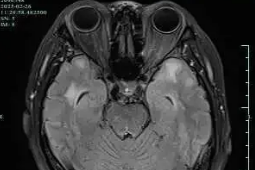

磁共振检查:解锁 CADASIL“密码”的钥匙

2025-04-17